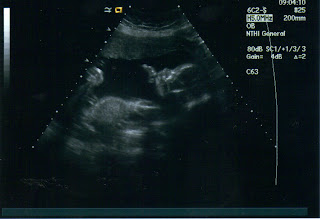

The doctor then left and returned with the Ultrasound machine. We would just have to find the baby that way and look at his/her heart. As soon as the machine turned on up popped the picture of the baby moving crazily about. I think he/she was celebrating having successfully avoided the heart detector. But he/she couldn't hide from the ultrasound. The doctor saw the baby's heart beating perfectly fine and took a picture for me. I then asked if he could determine the gender yet. He checked and said it definatly looks like a girl. But, after switching the camera said, "But that could be a penus right there."

I sighed, a little frustrated, but he explained to me that the ultrasound at the clinic isn't top of the line. But the one at the hospital is and they will be able to tell me the gender. Apparently I needed to make an apointment with them so they can measure all sorts of things on the baby anyway. So, as soon as I can I'll let you know the gender. I would post the ultrasound picture but the printer isn't working with the computer right now so I'll post it later! But as a side note. It looks like where Thomas has a rounded face this baby's face is more angular like his/her dad.